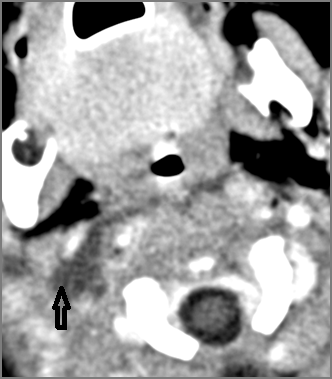

There is suppurative retropharyngeal lymphadenopathy. [Yes/No]

If there is suppurative retropharyngeal adenopathy what is the maximum short axis dimension of the largest suppurative node. Measurement [Yes/No]

There is suppurative cervical lymphadenopathy. [Yes/No]

If there is suppurative cervical adenopathy the purulent material outside the lymph node(s) capsule(s). [Yes/No]